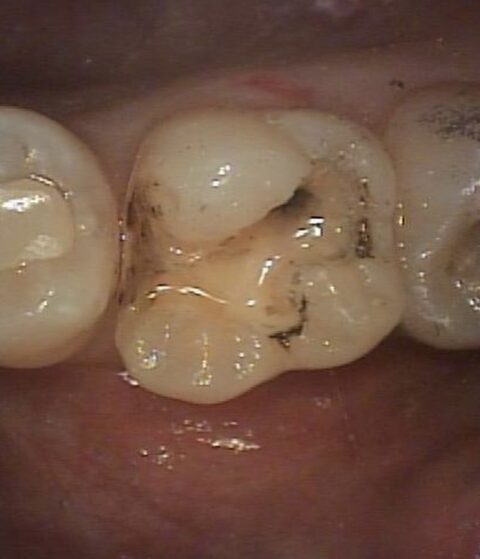

銀歯を外してみると、縁や内部で虫歯が発生しています。

■こちらの写真は虫歯を綺麗に取りきり、セラミックの為に形成した状態です。この後、セラミック作成の為の歯型取りに進んでいきます。

歯科治療は患者様には直接見えない治療となりますので、ドクターの精密な治療が予後に大きく影響いたします。

当院では、虫歯の取り残しがないよう精密な治療をし、口腔内写真を撮影してご説明させていただきながら治療を進めておりますのでご安心ください。